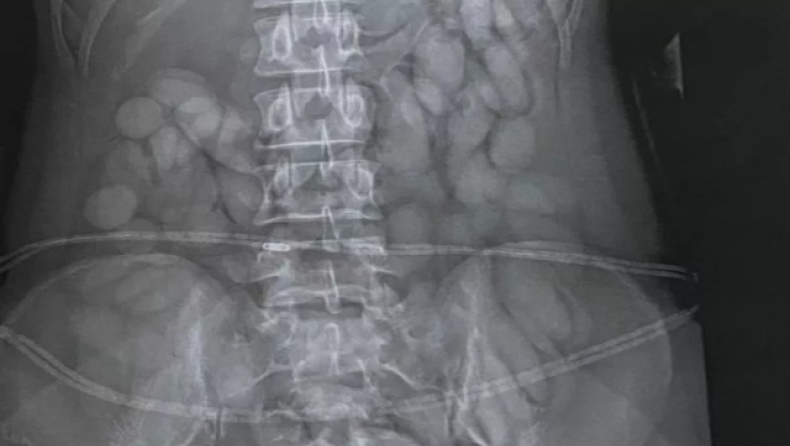

Μάλιστα, το «σκανάρισμα» του αεροδρομίου αποκάλυψε και την κρυψώνα της. Οι αστυνομικοί διαπίστωσαν ότι είχε καταπιεί δεκάδες «σφαίρες κοκαΐνης», με αποτέλεσμα να σταλθεί εσπευσμένα στο νοσοκομείο της πόλης για πλύση στομάχου. Εκεί, οι γιατροί διαπίστωσαν ότι η 30χρονη είχε καταβροχθίσει πάνω 60 «σφαιρίδια» ναρκωτικών.

Η εκπρόσωπος της εθνικής αστυνομίας Brig Athlenda Mathe ανέφερε: «Η ομάδα μας εντόπισε αμέσως το βαποράκι καθώς περνούσε από τη μεταναστευτική υπηρεσία. Συνελήφθη αμέσως, μεταφέρθηκε σε τοπικό νοσοκομείο όπου μια ιατρική ακτινογραφία εντόπισε ξένα αντικείμενα στο στομάχι της».